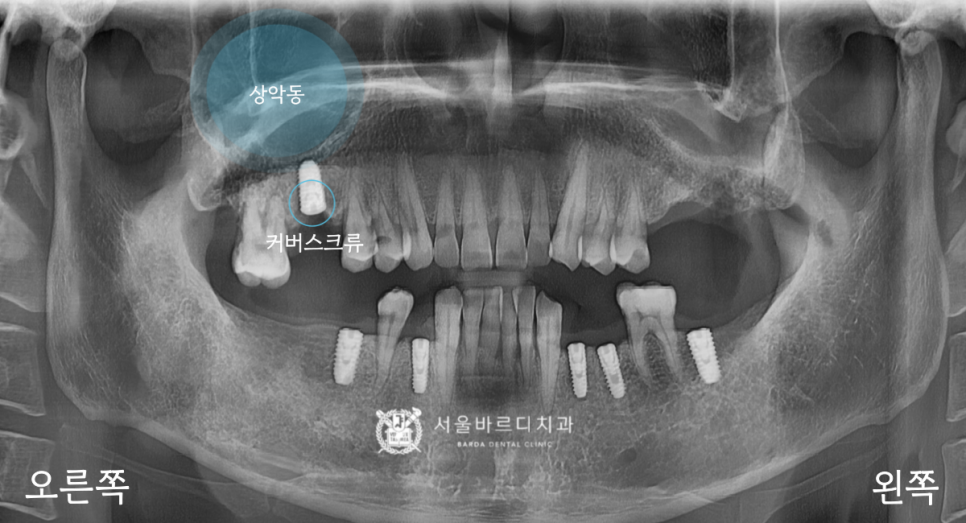

아래에 신경관이 있다면 위에는

상악동이라고 하는 공기주머니가 존재합니다.

얇은 막으로 둘러싸여 있어서

혹시라도 찢어지거나 뚫리게 된다면

축농증이 생길 수 있어서 조심하고 있습니다.

마찬가지로 가이드 장치를 장착하고,

해당 자리에 계획한 굵기와 길이의 픽스처를 심은 후

납작한 덮개인 커버스크류를 넣은 다음

잇몸을 잘 봉합해 드렸습니다.

20230223

왼쪽은 맨 뒤에 어금니가 상악동과 가까이 있어서

수압을 이용해 막을 들어 올려서 안쪽에 뼈를 채우는

상악동 수직 거상술을 통해 계획한 대로

긴 길이의 픽스처를 심을 수 있었습니다.